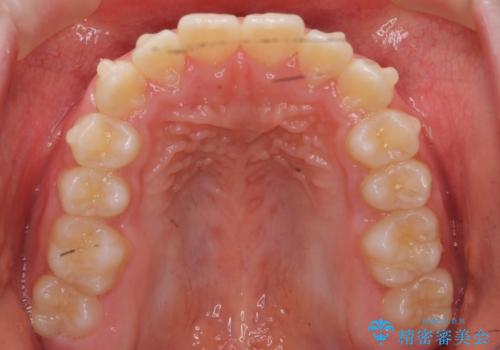

八重歯 歯を抜かずにインビザラインで

- 八重歯を主訴に来院。

抜かずに歯を少し削って入れる方法で並べました。

10代のうちに矯正をしておくと歯の移動は簡単で、歯ぐきも下がりにくいです。